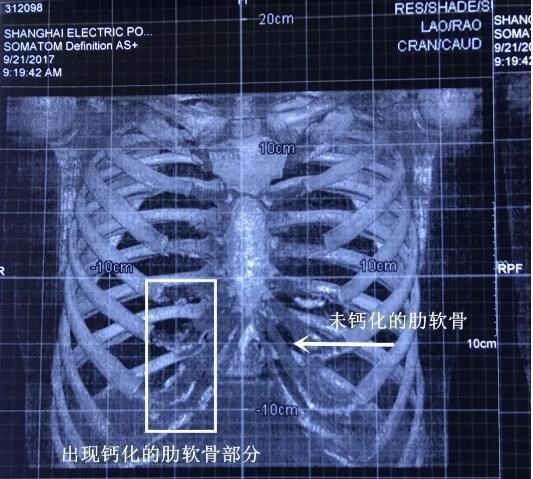

【卢丙仑琅丽】隆鼻材料之--钙化了的肋软骨

病情分析: 肋软骨症为肋软骨钙化现象,再X线片上显示为肋骨的胸骨端与胸骨之间有断续或连续的片状,条状,颗粒状或块状致密阴影. 如果为肋骨叉状畸形乃发育过程中正常变异,进入成年期以后的肋软骨钙化属正常现象. 指导意见: 现在患者正在确诊阶段,应该在医生的帮助下积极检查,以便及早治疗.如果患者为肋骨叉状畸形,则无需治疗,不必担心.